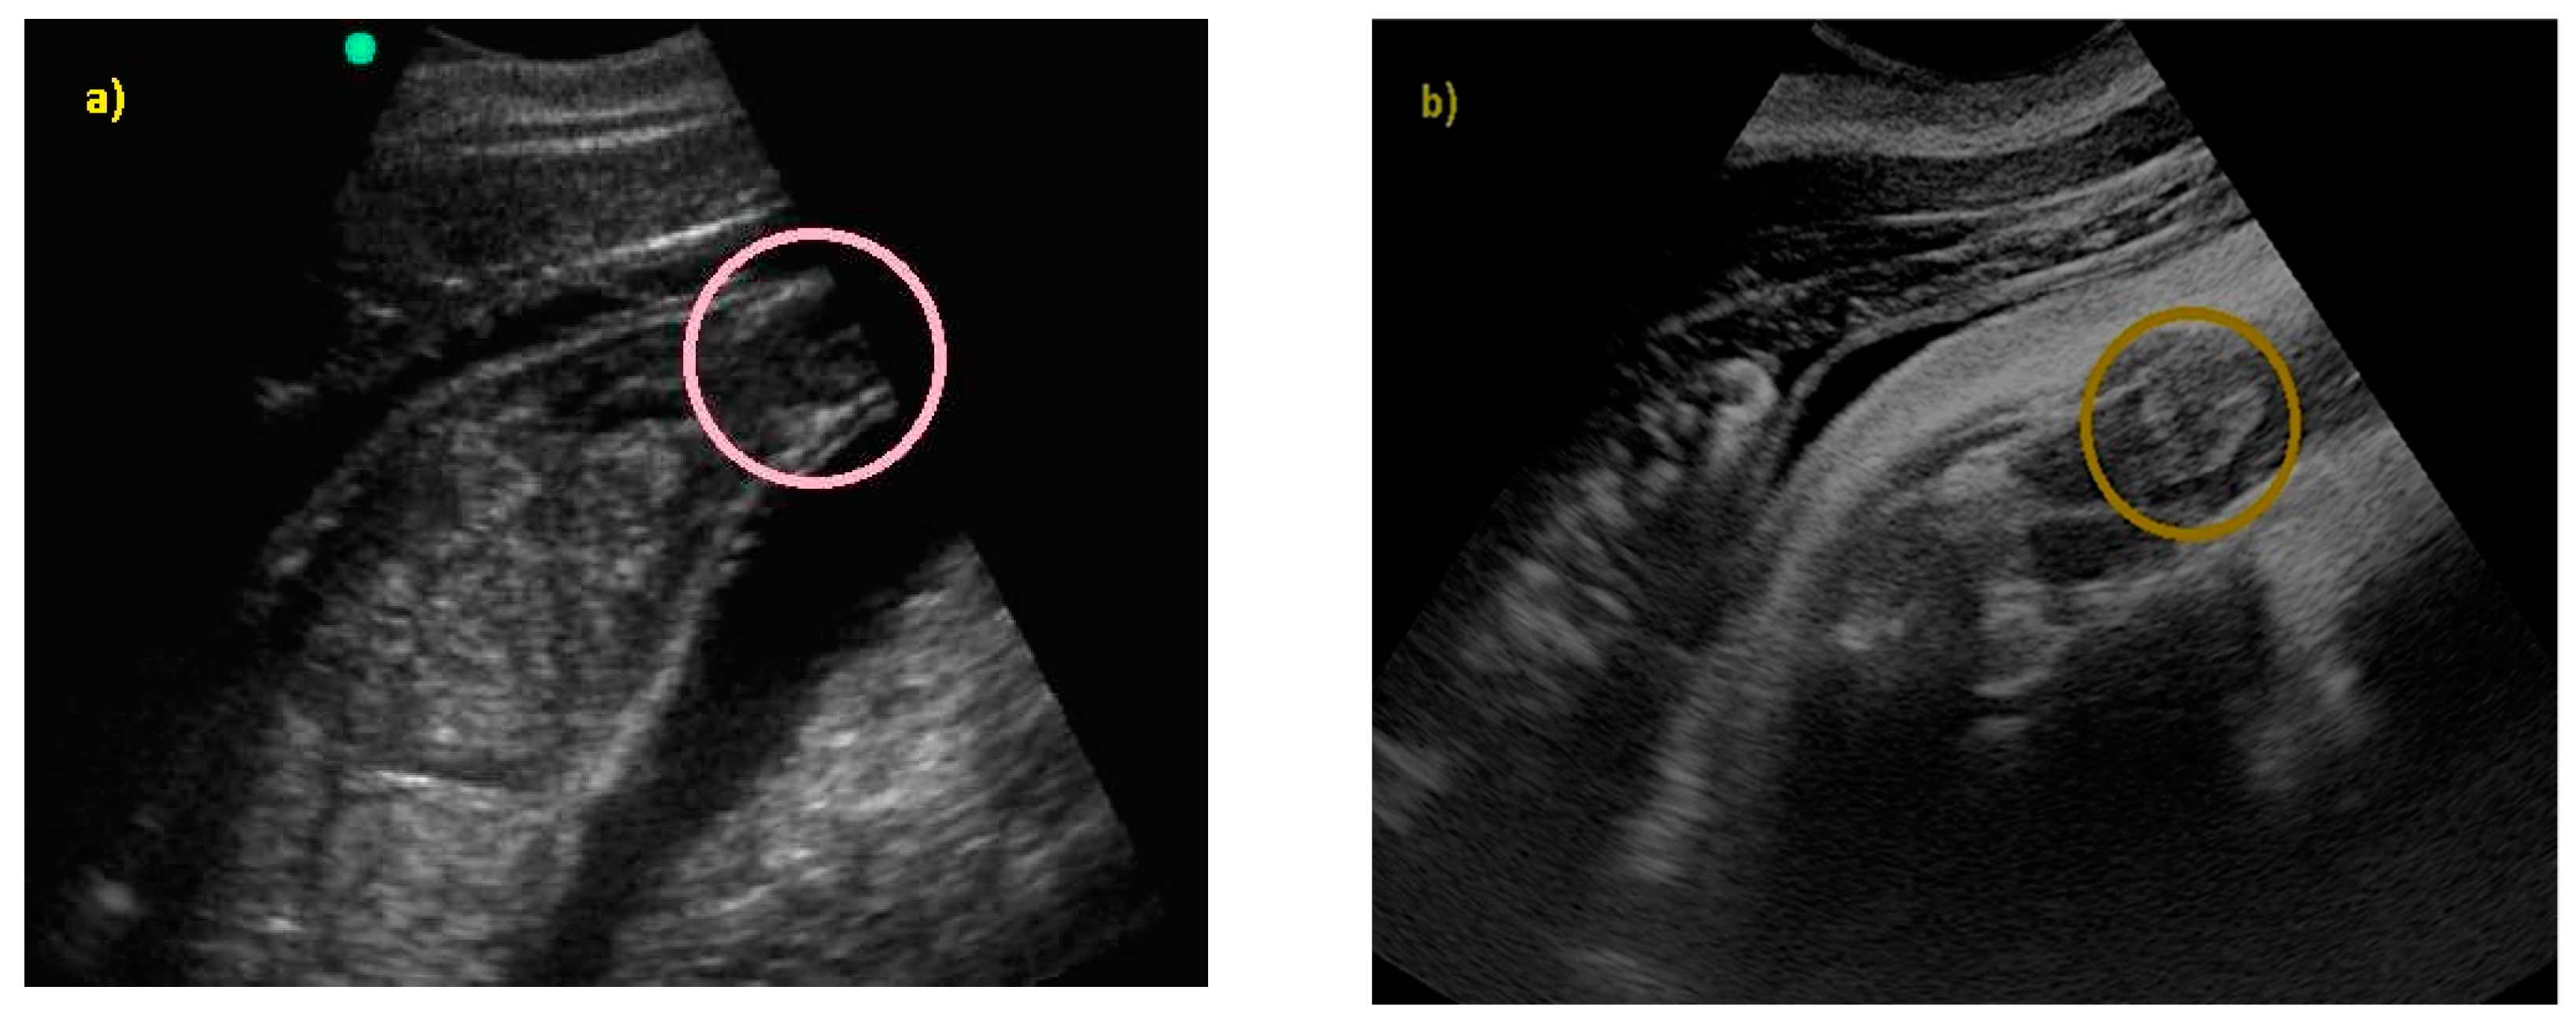

In addition, it was possible to identify the genitalia and sex the fetus (males have a tri-lobed structure, whereas females have an apricot-shaped structure, as shown in Figure 9).

Figure 9.

(a) An ultrasound image of female genitals (apricot-shaped) by SonoSite 180 Plus with a 2–5 MHz convex probe; (b) the same area caught with General Electrics Logiq V2, with a 2–5 MHz convex probe.